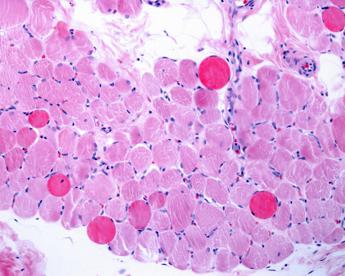

(Adnkronos) – Dalla ricerca italiana una nuova strategia per favorire la riparazione e la rigenerazione dei muscoli nei malati di distrofia di Duchenne. La scoperta, pubblicata su 'Nature Nanotechnology', porta la firma di un team di scienziati milanesi. Gli autori hanno sviluppato un metodo innovativo per veicolare in modo mirato nei tessuti muscolari distrofici microvescicole (esosomi) ingegnerizzate, con proprietà antinfiammatorie. La ricerca è coordinata da Chiara Villa e Yvan Torrente del Laboratorio di cellule staminali, Centro Dino Ferrari, del Dipartimento di Fisiopatologia medico-chirurgica e Trapianti dell'università Statale di Milano e dell'Unità di Neurologia del Policlinico cittadino, in collaborazione con i gruppi di Angelo Monguzzi (Dipartimento di Scienza dei materiali dell'università di Milano-Bicocca) e di Domenico Aquino (Dipartimento di Neuroradiologia dell'Irccs Istituto neurologico Carlo Besta di Milano). "La risoluzione dell'infiammazione nel contesto delle distrofie muscolari è una delle sfide più ardue che ricercatori e clinici cercano di risolvere", spiega Villa. Gli scienziati hanno trovato un modo per 'indirizzare' esosomi ingegnerizzati ad azione antinfiammatoria nei muscoli malati: utilizzando come vettore dei nanotubi ferromagnetici, questi esosomi possono migrare in maniera specifica nei muscoli danneggiati dalla distrofia muscolare di Duchenne (Dmd) tramite l'applicazione di un campo magnetico esterno dopo un'iniezione sistemica. "Siamo riusciti a controllare la biodistribuzione e il targeting degli esosomi in vivo al fine di ridurre la condizione infiammatoria dei muscoli colpiti dalla Dmd", sottolinea Villa. Le analisi quantitative a livello muscolare hanno mostrato che i macrofagi, un tipo di globuli bianchi, dominano l'assorbimento degli esosomi iniettati, promuovendo la rigenerazione muscolare e migliorando la performance dei muscoli in un modello murino di distrofia Duchenne. "I nostri risultati – commenta Torrente – forniscono nuove intuizioni per lo sviluppo di terapie basate su microvescicole naturali e sintetiche al fine di trattare diverse forme di malattie muscolari. In generale, evidenziano la formulazione di efficaci nanovettori funzionali mirati a ottimizzare la biodistribuzione delle microvescicole". Questa scoperta, si legge in una nota UniMi, rappresenta "un significativo passo avanti nel campo della medicina rigenerativa e delle terapie innovative per malattie muscolari. Il controllo preciso della biodistribuzione degli esosomi apre" infatti "nuove possibilità per il trattamento non solo della distrofia muscolare di Duchenne, ma anche di altre patologie muscolari caratterizzate da infiammazione cronica e degenerazione tessutale. La combinazione di nanotubi ferromagnetici ed esosomi ingegnerizzati potrebbe rivoluzionare l'approccio terapeutico, offrendo speranze concrete per pazienti e famiglie affetti da queste malattie debilitanti". —salutewebinfo@adnkronos.com (Web Info)